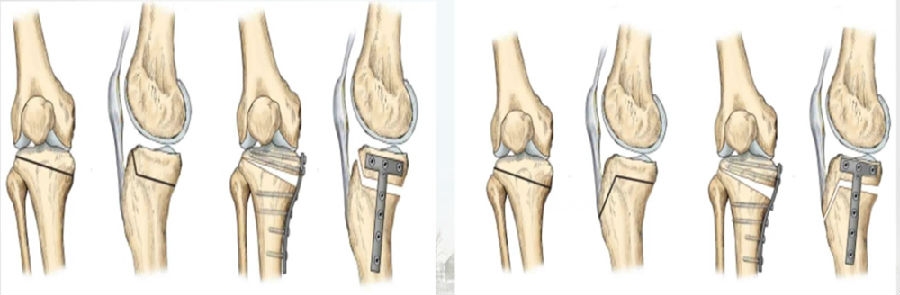

(1)OWHTO可分为上行性或下行性两种截骨方式。

(2)上行性OWHTO可降低髌骨高度的2%-11%;当髌骨高度下降10%,可引起髌股关节压力改变,引发膝前痛。

OWHTO上行截骨与下行截骨

(3)下行性OWHTO对髌骨高度影响较小。

(4)术前存在低位髌骨、髌股关节炎或内翻矫正度数较大时可考虑下行性OWHTO。